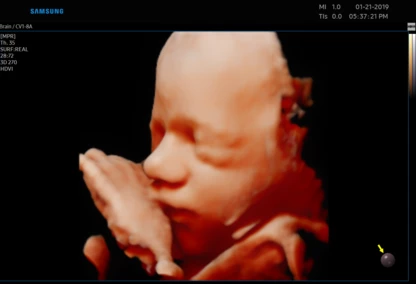

Każdą kobietę w ciąży otaczamy kompleksową opieką, czuwając nad jej zdrowiem oraz prawidłowym rozwojem płodu. Podczas regularnych wizyt, zlecamy odpowiednie badania laboratoryjne. Korzystając z najnowszej generacji aparatu USG, przeprowadzamy bardzo dokładną diagnostykę obrazową – łącznie z USG 3D/4D płodu.

• Najnowsza generacja aparatu USG pozwala na przeprowadzanie dokładnej diagnostyki obrazowej, diagnostyki przepływów (Doppler).